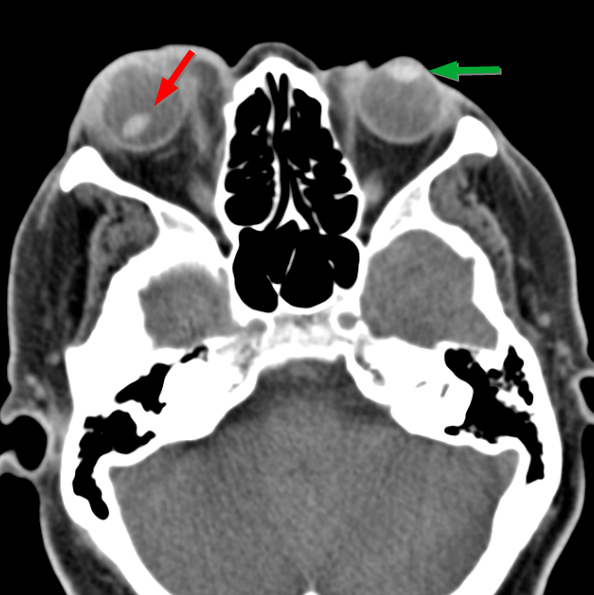

안과적인 특징은 공모양소수정체(spherophakia)입니다.

즉, 수정체가 찐빵과 같은 모양으로 넙데데하게 생깃것이아니라,

공모양으로 둥굴게 생겼습니다.

즉, 수정체 지름은 감소되어있고, 두께는 증가되어 있어

동공을 산동시켜보면 수정체의 전체 모양이 완전히 관찰가능합니다.

이 공모양 수정체가 탈구를 일으켜 동공과 맞닿는 경우,

2차적인 동공폐쇄 녹내장을 일으킬수 있습니다.